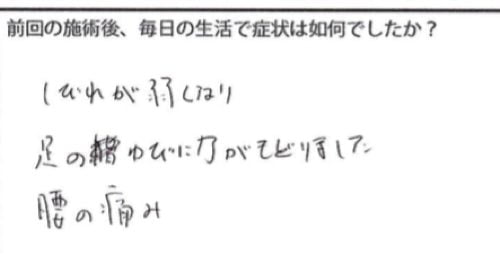

現在の状況を書いて頂くと

両足の痺れ

腰は一定以上に動かすと痛み

足の指に力が入らない為 歩行がしづらい

そんな状態です。